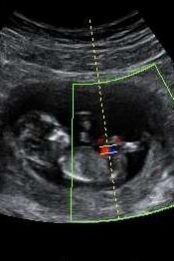

Ontem completei 50 partos que atendi como doula. Em cada um deles, aprendi tanto sobre superação de limites, cura de feridas, entrega, perseverança, cumplicidade, medo e coragem. Acompanhar uma mulher em trabalho de parto exige tanta delicadeza! As 50 mulheres que tive a honra de ajudar a colocar um bebê no mundo me mostraram que cada parto é único e, por isso, meu olhar deve ser atento ao que cada uma precisa.